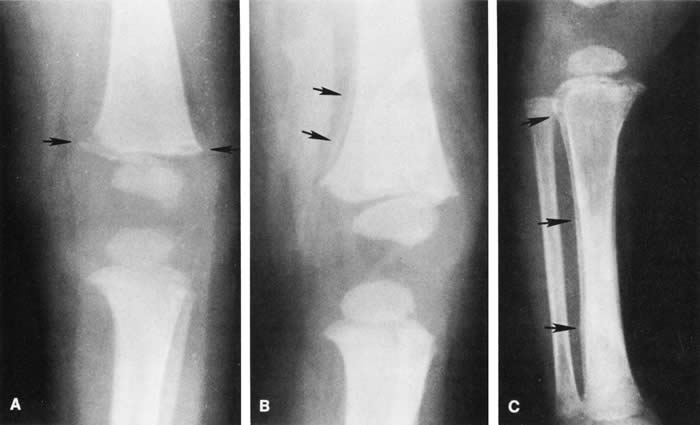

Skull fractures occur in 9% to 31% of shaken babies,23,30 with the parietal and occipital bones most affected. The characteristics of skull fractures that are highly suggestive of abuse include branching, stellate, crossing suture lines, multiple, greater than 5 mm wide, or progressively expanding fractures in a child less than 3 years of age.29 Rib fractures are the most common bone injury in SBS, and are usually posterolateral due to the perpetrator's hands grasping the child. Long bone fractures affect the tibia, forearm bones, femur, or humerus in decreasing order of prevalence. The characteristic metaphyseal fracture, which rarely occurs in young children except in the setting of abuse, results in a “corner” or “bucket handle” chip fracture at the end of the bone (Fig 9). Other injuries seen in SBS include hemorrhagic stripping of the periostium, spiral fractures, and nonsupracondylar humerus fractures—all due to shaking while the infant is held by an extremity, causing the long bones to be twisted and broken.29,30

Fig. 9. Epiphyseal-metaphyseal fractures as seen in shaken baby syndrome: stages of healing. A. Fresh fracture (less than 10 days). Note rarefaction of the bone underneath the epiphyseal plate (short arrow). B. Appearance of fracture at 10 days to 2 weeks. Note early periosteal new bone deposition (long arrows). C. Appearance of fracture at 2 to 4 weeks. Note more pronounced periosteal new bone deposition and epiphyseal-metaphyseal changes characteristic of this stage of healing. (Swischuk LE: Radiology of the skeletal system. In Ellerstein NS [ed]: Child Abuse and Neglect: A Medical Reference. New York, John Wiley & Sons)